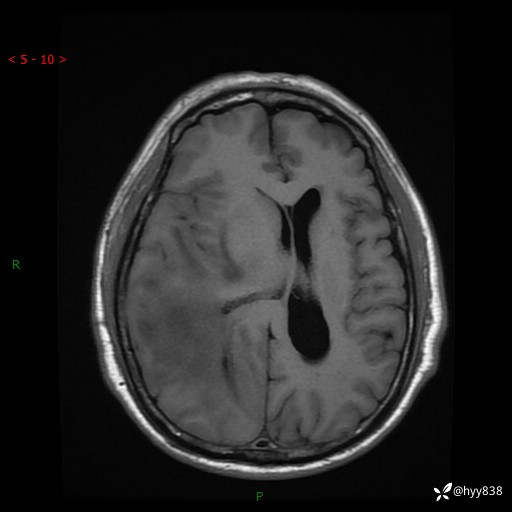

患者性别:男

患者年龄:56岁

简要病史:外院CT提示脑膜瘤,为进一步诊治来我院

辅助检查:MRI

临床诊断:颅脑占位

颅脑MRI平扫+增强